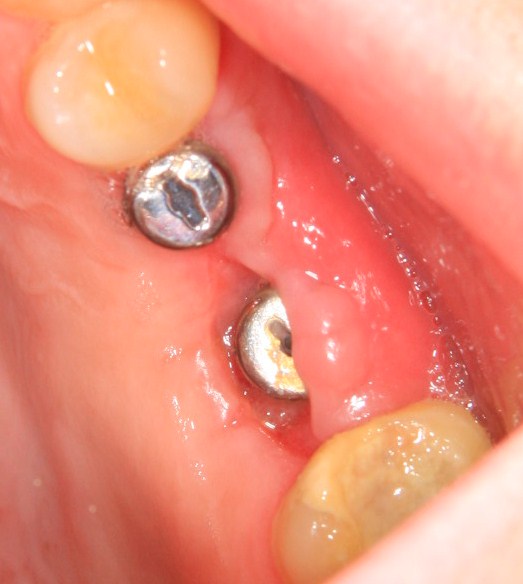

Немедленная имплантация — оптимальное решение в любой клинической ситуации